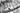

Имплантация в области 26 зуба.

Пациент направлен доктором ортопедом из другой клиники на установку импланта Astra tech в область давно утраченного зуба.

В ходе диагностики мы понимаем: уменьшение длины зубного ряда за счёт мезиального смещения зубов 27 и 28.

Мы можем прогнозировать, что будущий зуб будет меньшего размера чем должен.

Было предложено смещение зубов с помощью ортодонтических микровинтов.

К сожалению, пациент отказался от локальной ортодонтии.

Мне не очень нравятся такие операции, потому что я знаю возможности моей команды и знаю какой возможен результат!

Но лечащий доктор и пациент были за упрощённую схему восстановления...